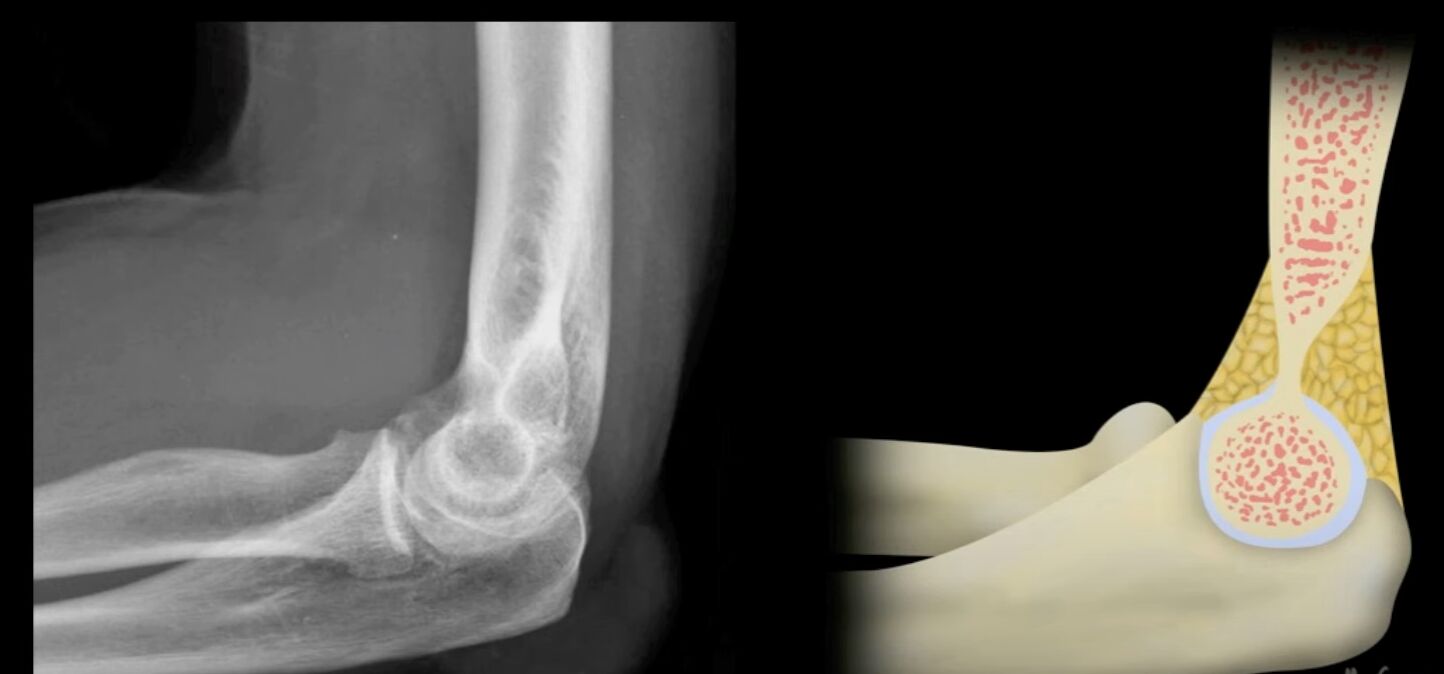

72.病人跌倒後被送到急診室,左手肘劇烈疼痛且無法活動。他的左手肘X光片側面照的影像如圖所示,下列敘述何者最恰當?

(D)可明顯發現關節積液(joint effusion)

老實說,開書我還是看不出來。但你看到elbow沒有明顯骨折8成在考你fat pad sign

附一張正常的示意圖